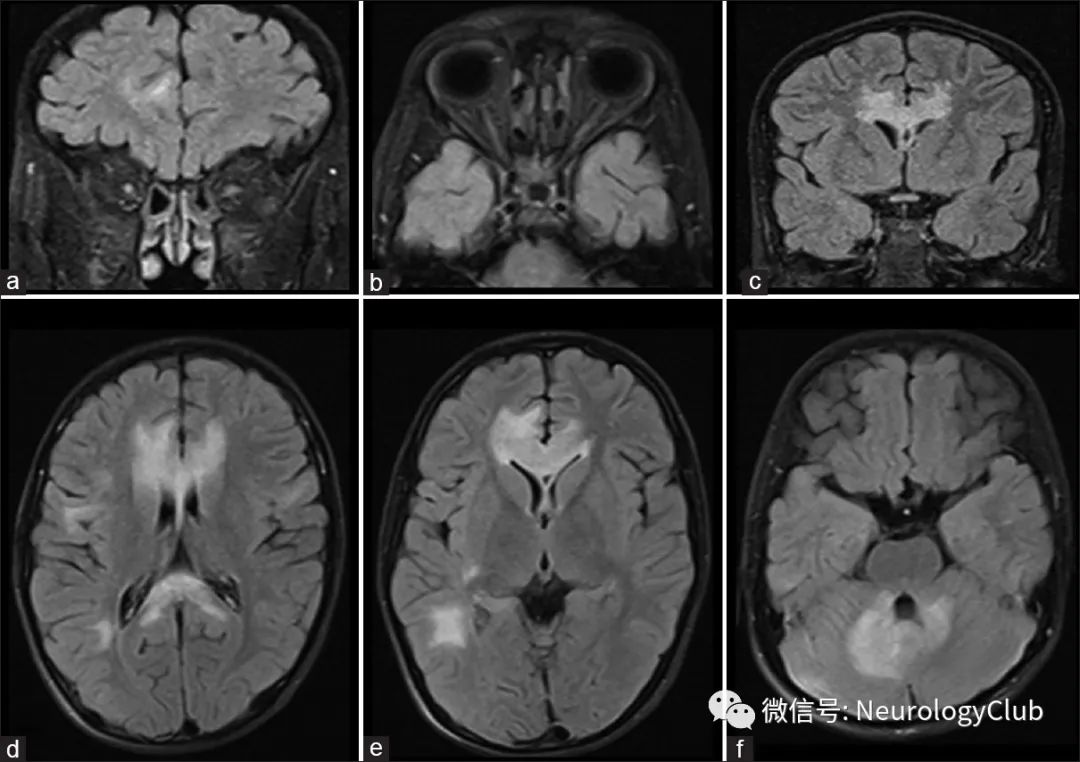

MOG-AD脑部病变表现为少量“蓬松”的、界限不清的或者大片的T2WI高信号,增强扫描病变不强化或者呈松散的结节状、斑片状、条状或开环状强化(图2D-F)。Komatsu等发现白质病变可出现血管周围强化,类似胶质纤维酸性蛋白星形细胞病相关的原发性炎症或脑炎。部分病变表现为软脑膜强化,类似脑膜炎。胼胝体病变往往呈局灶性、离散性的结节状病灶,在脑室周围没有特定的方向。部分以癫起病者表现为皮质脑炎,可见特有的皮质液体衰减反转恢复(FLAIR)序列高信号,称为“FLAMES”(FLAIR-hyperintense lesions in anti-MOG-associated encephalitis with seizures),在DWI序列上病灶显示不佳,可以与癫痫导致的脑部异常相鉴别。Miyaue等、Shu等报道的3例MOG-AD影像表现类似肿瘤样脱髓鞘,脑组织活检病理类似多发性硬化。

补充图4:a:FLAIR COR图像可见双侧前段视神经高信号,提示视神经炎;b:FLAIR轴位图像可见双侧视神经纵向广泛高信号;c:FLAIR COR图像可见视交叉和胼胝体前部高信号;d-e:FLAIR轴位图像可见弥漫性大而蓬松的胼胝体和皮质下高信号;f:FLAIR轴位图像可见双侧小脑齿状核和小脑中脚高信号;引自:Neurol India. 2020 Sep-Oct;68(5):1106-1114.